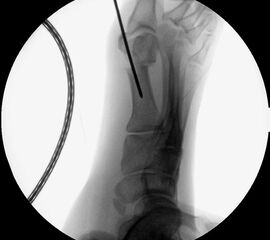

• Lagerung des Beins auf einem gepolsterten Untergrund. Positionierung des Bildverstärkers im 90° Winkel zur Fußlängsachse (Abbildung 4).